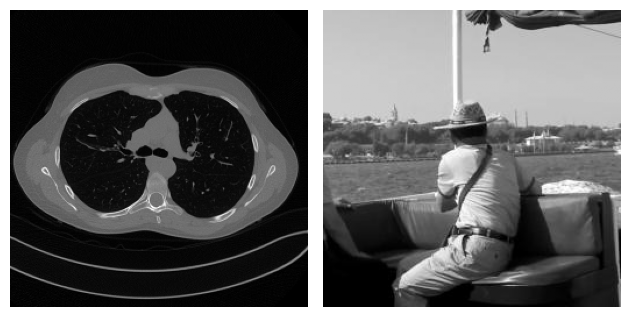

For example, consider the following problem, where two images coming from two completely different datasets are corrupted by Gaussian blur and noise. By looking at both the true image and the corrupted image, it is clear that the content of the two examples is very different. On the other hand, when we look at the residual, i.e. the value \(|x_{true} - y^\delta|\), the patterns in the two images look similar.

This observation justifies that learning the residual is usually easier (and generalizes better) than learning the actual image.